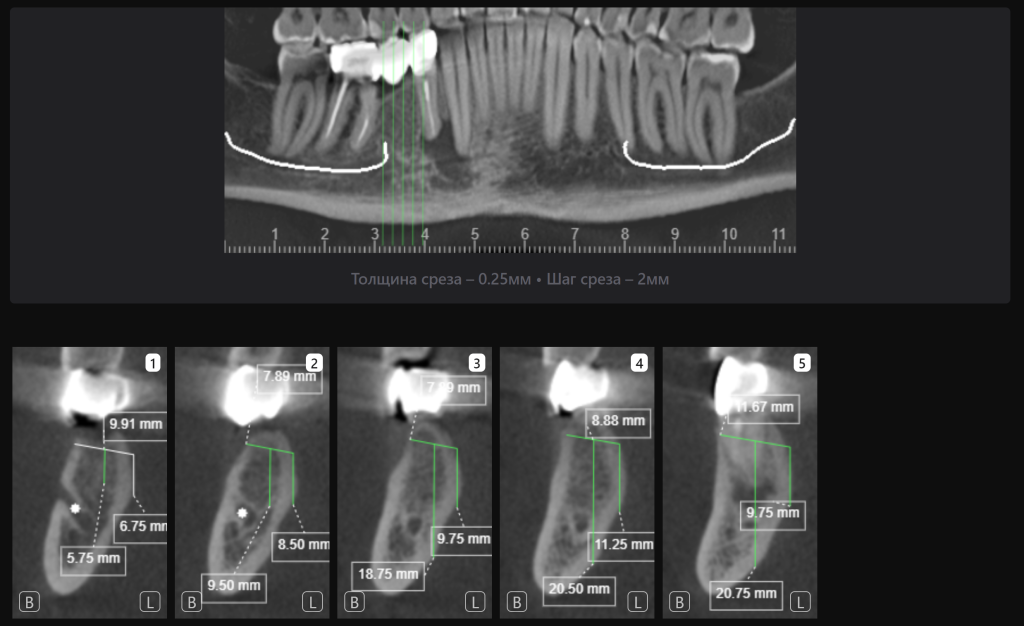

«Эндодонтический отчет» Diagnocat помогает зафиксировать изначальный объем периапикального очага и изучить анатомию и морфологию корневых каналов до начала лечения

Проведено повторное эндодонтическое лечение зуба 4.4

Через 12 месяцев мы видим положительную динамику после проведенного эндодонтического лечения зуба 4.4 и благоприятную ортопедическую позицию имплантатов